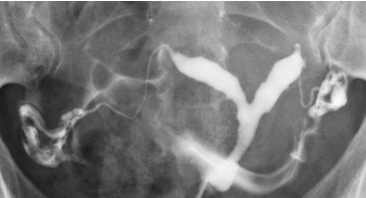

HSG Normal com Espalhamento Bilateral

HSG normal mostrando cavidade uterina, ambas as tubas preenchidas e espalhamento peritoneal livre (Cotte positivo bilateral).

Um exame normal mostra uma cavidade uterina triangular com contornos lisos, tubas uterinas finas e sinuosas preenchendo-se progressivamente, e um espalhamento livre e bilateral do contraste na cavidade peritoneal.